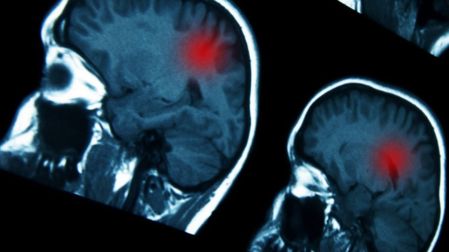

- Existen dolores de cabeza, mareos, crisis convulsivas cuando el cáncer se diseminó al encéfalo (cerebro)